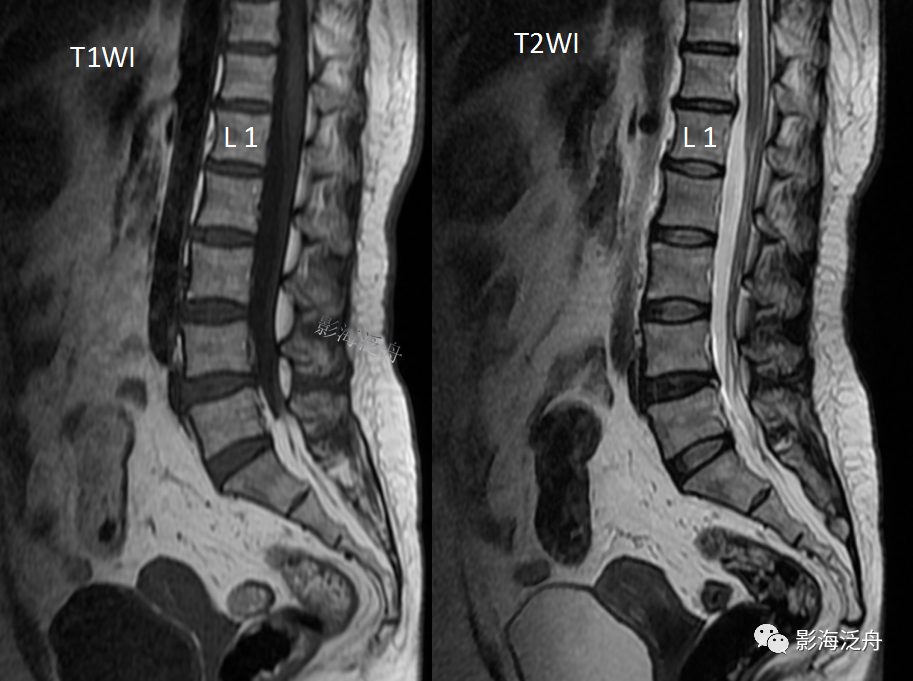

两次检查可以看到整个腰椎骨质结构的退变并不明显(毕竟人家芳龄才30

),椎间盘退变以L4/5水平为著(髓核退变、脱水后在T2WI上信号减低),但椎间盘的突出程度并不严重,一般来说不太可能引起明显的临床症状。那患者多年的腰疼症状到底是什么原因造成的呢?

如果没看出来,我把两张图放一起